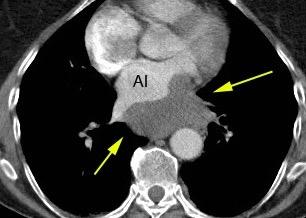

6. ÁREAS DEL MEDIASTINO EN TC